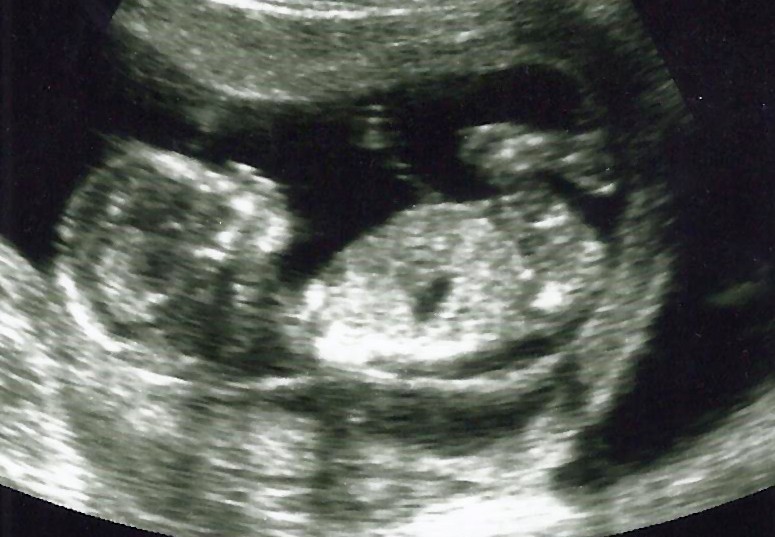

I have not found any studies yet with a woman going on life support at 9 weeks. However, Adriana’s baby has made it to 21 weeks and even now has a chance of survival outside of Adriana’s body.

Additionally, the newer ultrasounds show baby Chance is in good health and developing normally, even being slightly above average in weight for his age.